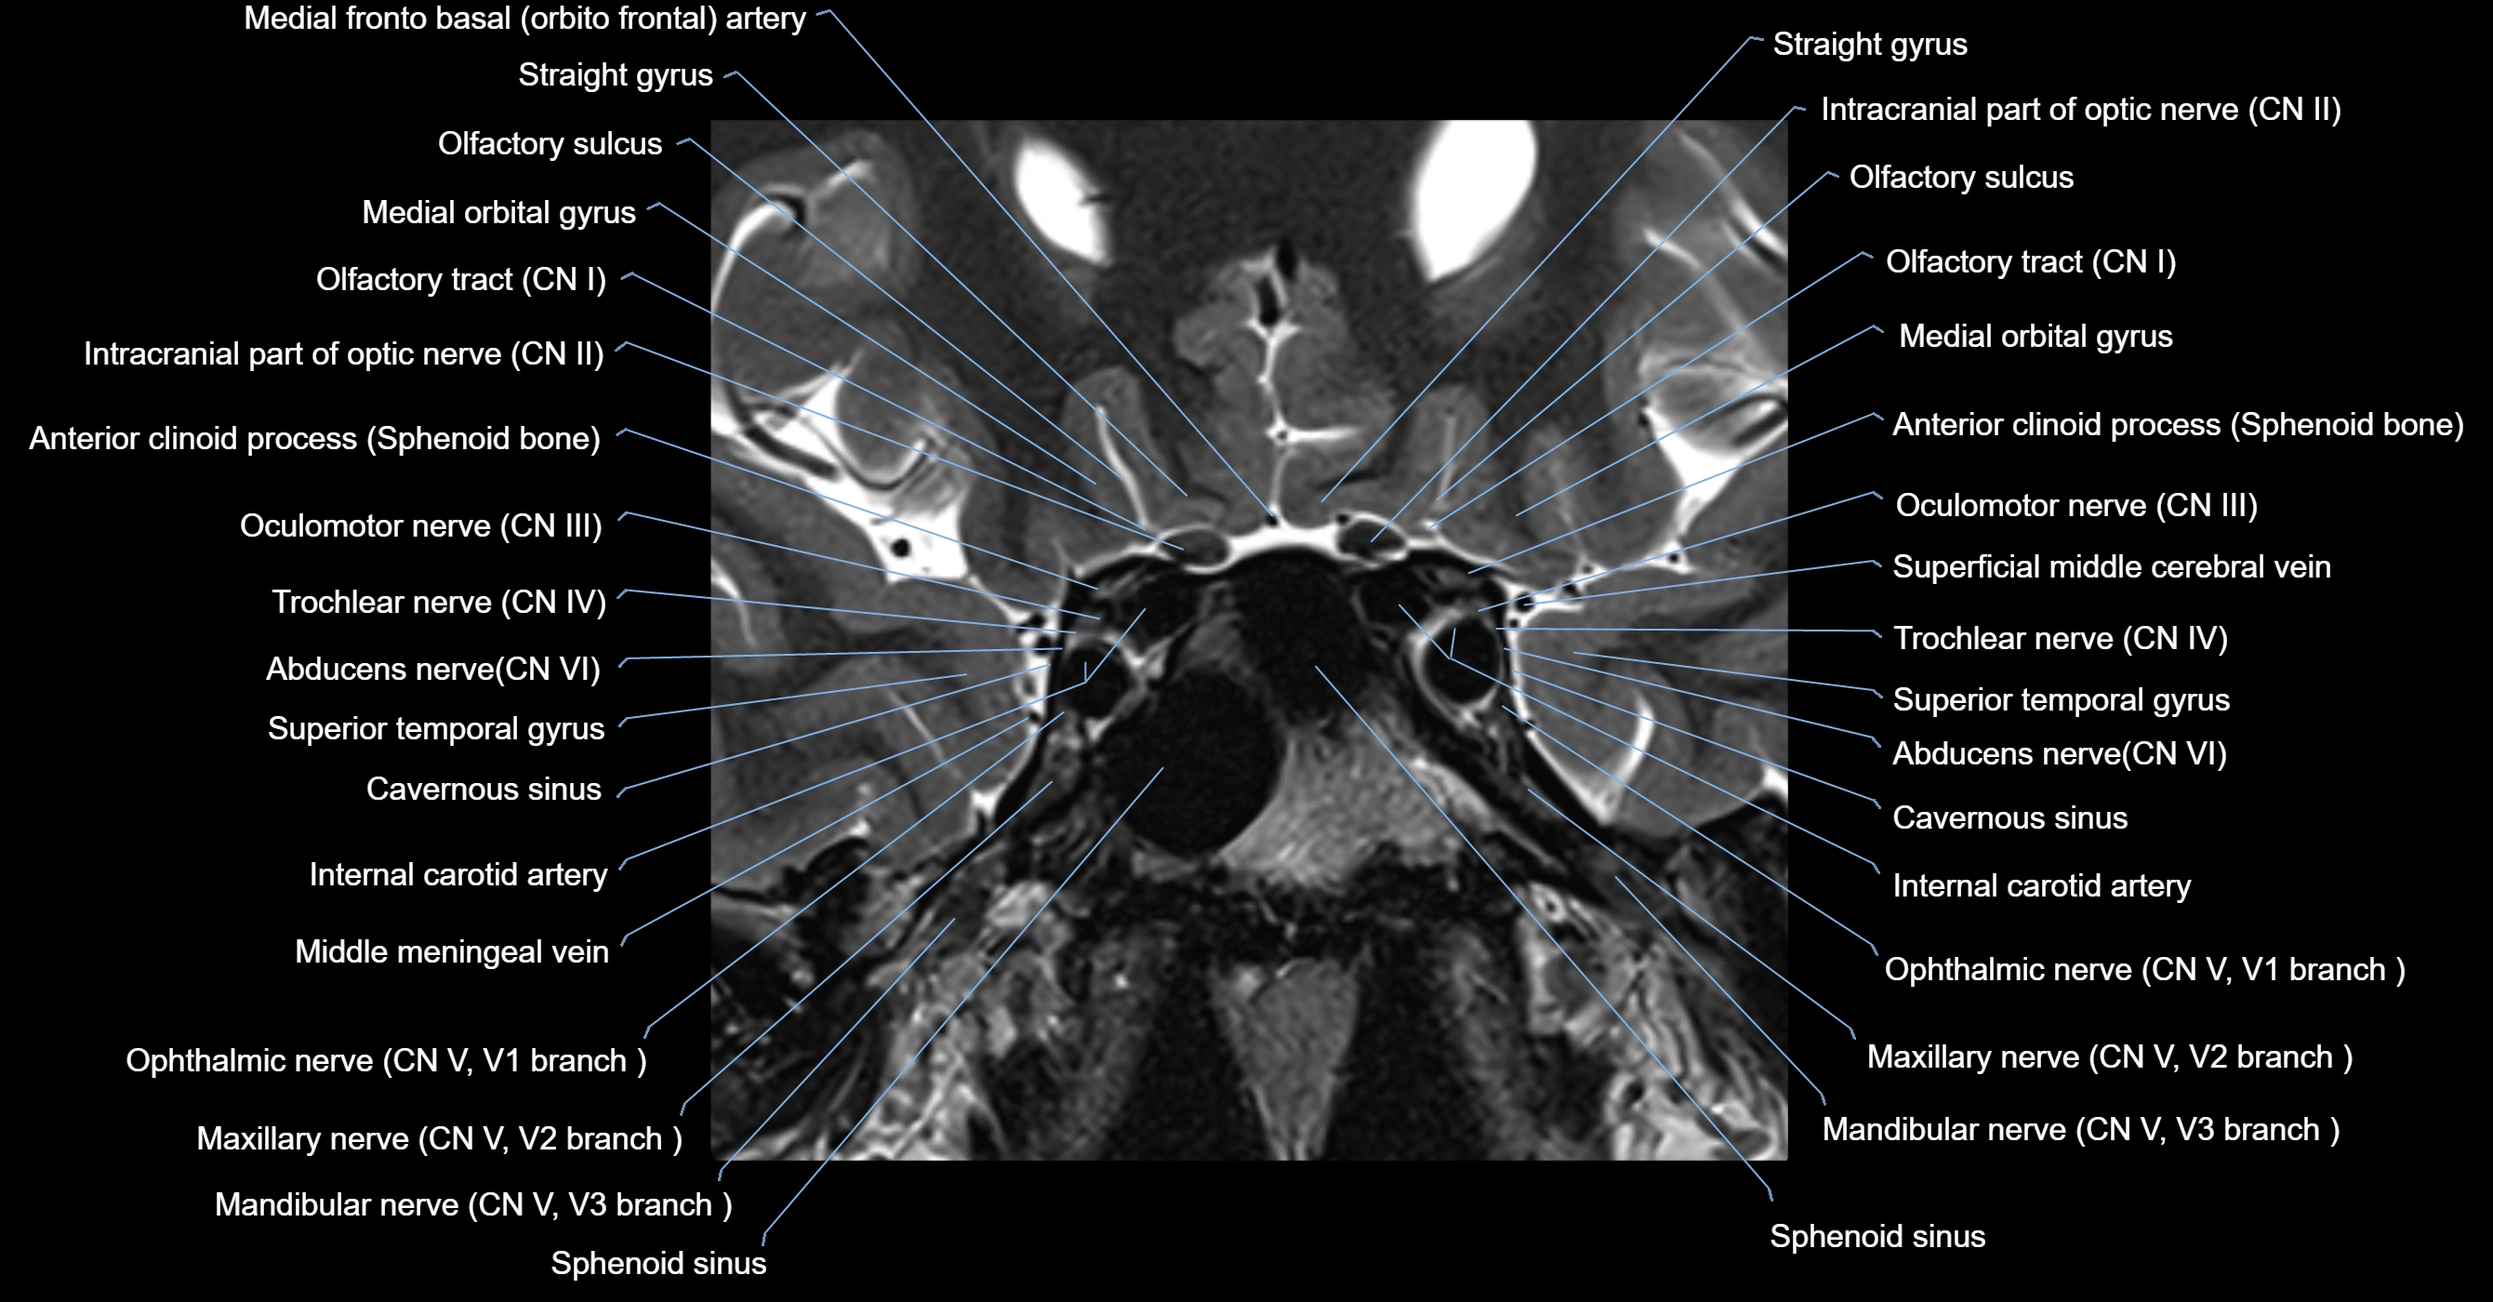

MRI Appearance

-

The abducens nerve is a small, thin, linear structure

Best visualized on high-resolution T2-weighted 3D MRI sequences (e.g., FIESTA or CISS)

Seen as a hypointense (dark) line running from the brainstem at the pontomedullary junction, traversing the prepontine cistern, and entering Dorello’s canal under the petrosphenoidal ligament, then into the cavernous sinus, and finally the orbit

May be challenging to visualize in standard MRI due to its small size

Pathology may be inferred by absence, displacement, or enhancement of the nerve

MRI images